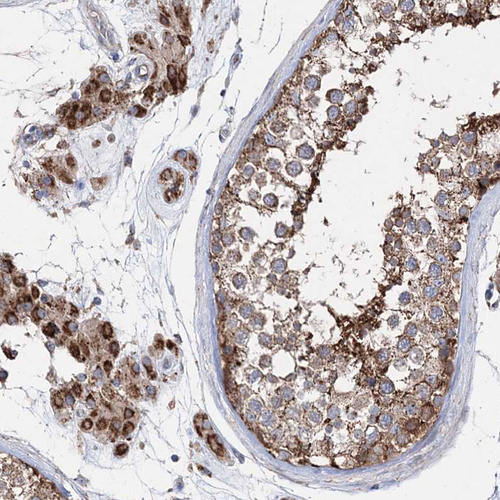

Immunohistochemical staining of human testis shows moderate to strong granular cytoplasmic positivity in cells in seminiferous ducts and Leydig cells.